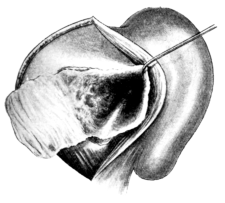

| 71. | Vaginal Hysterectomy | 171 |

| 72. | Vaginal Hysterectomy. Final stage | 172 |